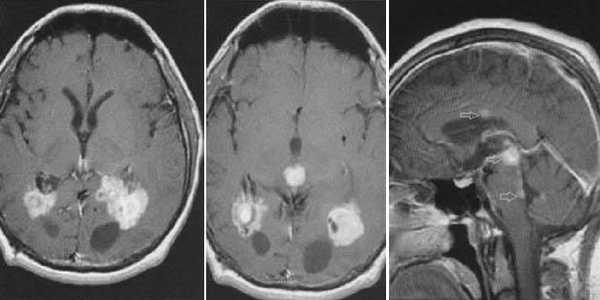

Злокачественная смешанная герминативноклеточная опухоль. В боковых желудочках и пинеальной области определяются множественные опухолевые узлы с выраженным перитуморальным отеком. Внутрижелудочковые образования с признаками кровоизлияний. При в/в контрастировании определяется выраженное контрастирование узлов. Дополнительно визуализируется метастазирование по эпендиме боковых и IV желудочков мозга.

Глиобластома зрительного бугра справа. До и после в/в контрастирования определяется объемное образование с некротическим центром и контрастируемой периферической инфильтративной частью. Деформированы задние отделы III желудочка, начальный проявления окклюзионной гидроцефалии.